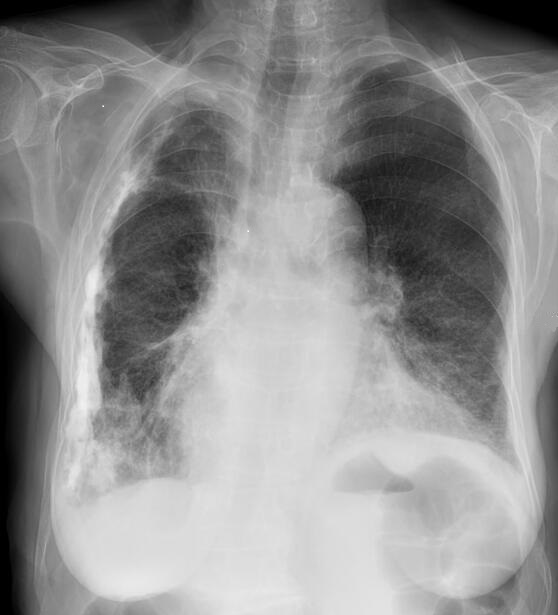

Image

calcification en plaque diffuse d'une ancien

tuberculose pleuro -pulmonaire droit . On peut en

vue encore de lesion ancienne tuberculeuse

fibrotique restrictive du poumon droit |

Image radiologique PA d'une pleurésie

purulente chronique du poumon droit . Aspect

radiologique est de plaque fibrosant et

calcification de la plevre du poumon droit .

L'espace intercostale droit est pince , la volume du

poumon droit est diminue et restrictive |